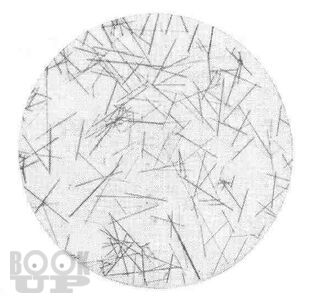

В соответствии с рабочей программой по токсикологической химии, изложен материал о методах изолирования, свойствах и определении «металлических ядов». В пособие представлена информация о катионах, которые в настоящее время имеют наибольший токсикологический интерес, изложены основы дробного исследования, его особенности. При описании большинства методик анализа приведены уравнения химических реакций, применяемых для выявления этих катионов. Кратко представлена информация, необходимая по данной группе веществ.